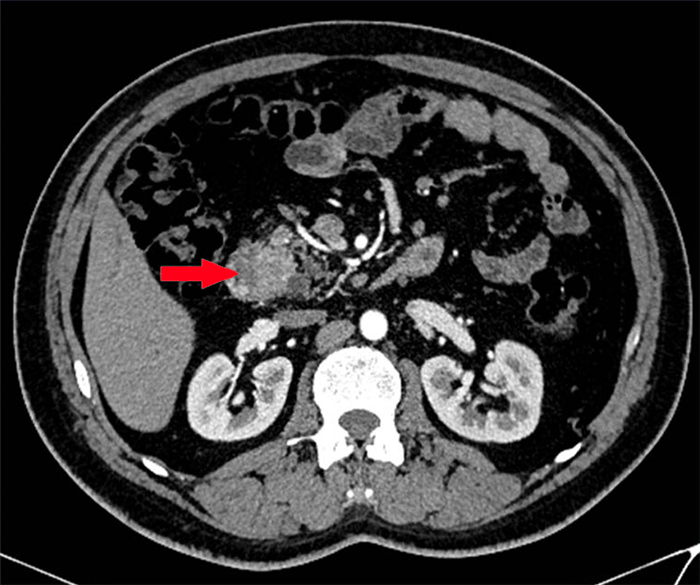

CT(電子計算機(jī)斷層掃描)檢查

經(jīng)過與患者詳細(xì)溝通,醫(yī)生為患者進(jìn)行了CT、MRCP、胃鏡等相關(guān)檢查,以明確患病原因、病灶位置等情況。經(jīng)相關(guān)檢查及醫(yī)生診斷,患者被診斷為十二指腸腫瘤,而且腫瘤已經(jīng)侵犯到胰頭。